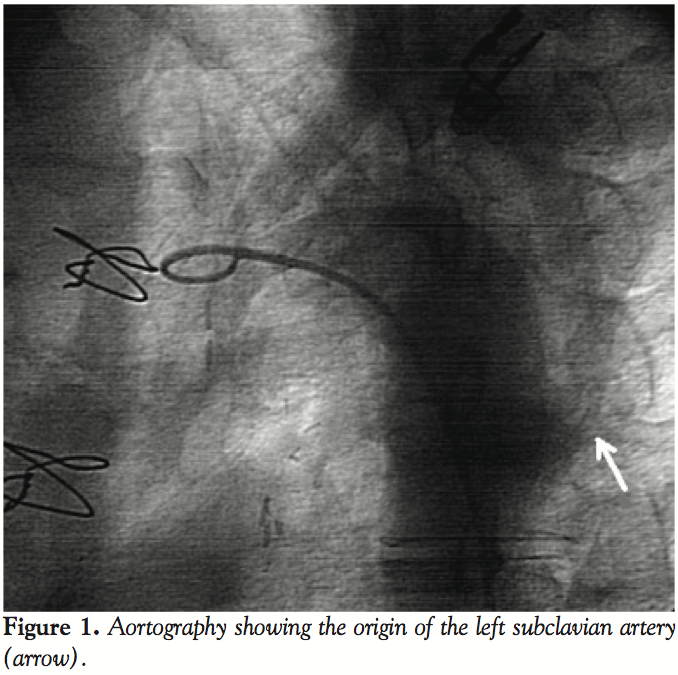

However, many attempts to visualize the bypass grafting of the left internal mammary artery (LIMA) to the LAD failed as the left subclavian artery could not be engaged at aortic arch. After an aortography, we found that the ostium took its origin 5 cm below its presumed position (Figure 1). Thereafter, the left subclavian artery was successfully engaged with a Judkins right 4 catheter and the LIMA was selectively cannulated to check distal patency (Figure 2). Percutaneous interventions for significant occlusions in the left circumflex and right coronary arteries were successfully performed without any complication. No other congenital anomaly was detected in the patient. He was discharged uneventfully on post-admission day 4.